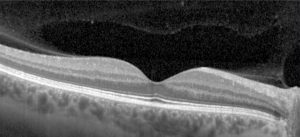

La tomografia a coerenza ottica (OCT) è un test di imaging non invasivo che utilizza le onde di luce per scattare foto della retina, e in particolare della macula. La macula è una parte della retina deputata alla visione a colori e ad alta definizione.

Con l’OCT possono essere analizzati e mappati tutti gli strati retinici, inoltre è possibile rilevare lo spessore retinico. Questi dati aiutano a effettuare una corretta diagnosi e a fornire delle indicazioni per il trattamento del glaucoma e delle patologie retiniche, malattie come la degenerazione maculare senile e la retinopatia diabetica.